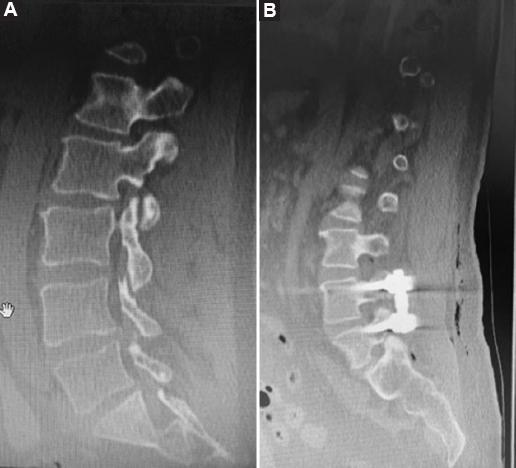

A retrospective review of 98 patients who underwent posterior stabilization surgery with a posterior approach in our clinic between 2018 and 2023 was conducted. The patients were divided into two groups based on the type of implant used: Those with PLSRR (Group 1, Fig. 1) and those with PLSDR (Group 2, Fig. 2).

All surgeries were performed by the same surgical team and similar techniques were used for both groups. After general anesthesia, patients were positioned in the prone position and an incision was made in the posterior midline. Muscles were dissected to reveal the bone structures. In Group 2, pedicle screws were placed first and the placements of the pedicle screws were checked under fluoroscopy. After placing the dynamic rod system, a laminectomy was performed to achieve decompression, and it was ensured that the medial facet joints were preserved as much as possible. For many patients, basic decompression was performed, but in cases of significant narrowing, extensive decompression was required. In cases with lumbar disk herniation, partial discectomy and foraminotomy were performed (Fig. 3)10,11.